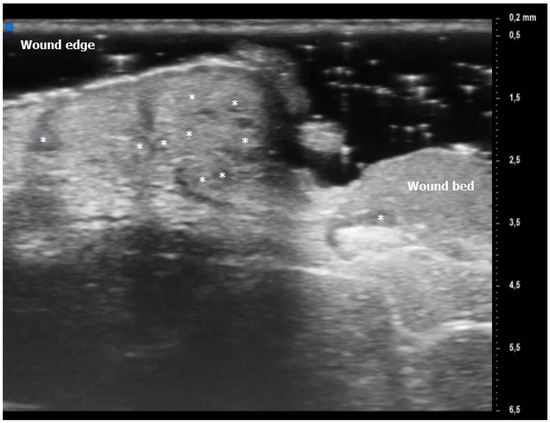

Figure 4. Patient affected by ulcerative Pyoderma Gangrenosum (PG) of the calf during the inflammatory phase: clinical aspect of the wound and its Ultra-High Frequency UltraSound (UHFUS) correlates.

The results obtained by our investigation revealed some UHFUS differences between the inflammatory and non-inflammatory phases. At T0, oval hyperechoic structures, that statistically significantly decreased in T1, were identified in the papillary and reticular dermis (p-value < 0.05) (Figure 4 and Figure 5).

Oval hyperechoic structures were identified in the reticular and papillary dermis during the initial T0 UHFUS examination. These structures were surrounded by a consistent, homogeneous hypoechoic background. Notably, this peculiar arrangement was observed in both the pustular and ulcerative phenotypes, indicating a common underlying feature.

As the examination progressed towards the inflamed edge, these oval structures exhibited a noticeable increase in prevalence, reinforcing their association with the inflammatory process.

A statistically significant decrease in the presence of these hyperechoic oval structures was observed during the subsequent T1 UHFUS examination. This reduction in prevalence (p value < 0.05) underscores the dynamic nature of these structures and their potential correlation with the progression of the inflammatory response (Figure 2).